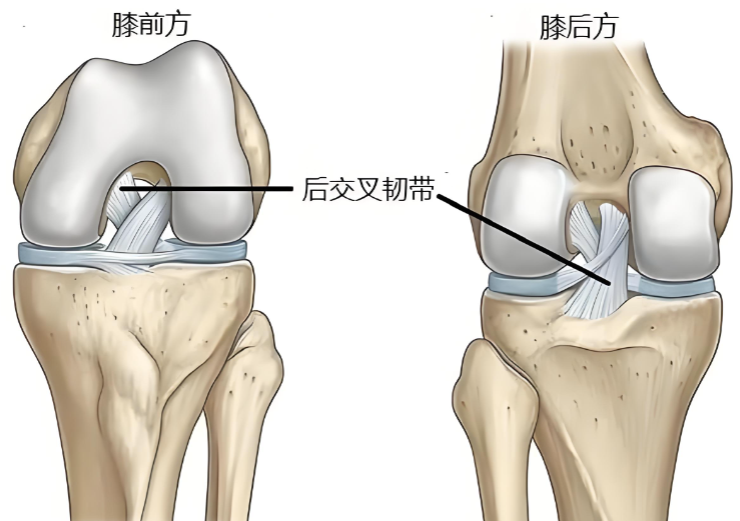

后交叉韧带位于膝关节最深部,起自股骨内髁外侧面前部,向后下方延伸,止于胫骨平台后方斜坡。该韧带比前交叉韧带更粗大和强壮。

后交叉韧带的主要功能是抵抗胫骨后移,作为防止小腿骨相对于大腿骨向后错位的最主要结构,在上下坡、下楼梯和减速奔跑时起着关键的稳定作用。